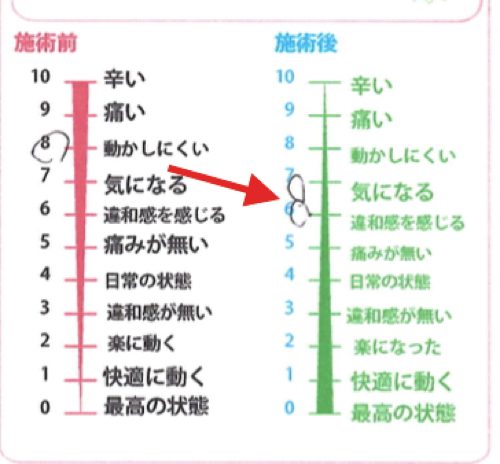

施術前後のアンケート

施術前 8:動かしにくい → 施術後 7氣になる 6違和感を感じる

施術後はシビレが若干弱くなり 足指に少し力が入るようになりましたが少し違和感があって氣になる感じです。

それは何故かというと

何ヶ月も硬直してヨジレていたりズレていたりした筋肉や腱を

今 正しい位置に戻したばかりなので違和感を感じるのです。

正常な状態を忘れていてさっきまでのズレている位置が標準になってしまっているからです。